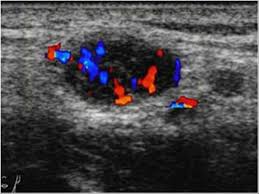

Enlarged Lymph Nodes In Head And Neck Cancer Analysis With Triplex Ultrasonography Sathyanarayan V Siva Bharani K Ann Maxillofac Surg from www.amsjournal.com Ultrasound an ultrasound is sometimes used, especially to look at the thyroid, salivary glands and lymph glands in the neck. Ultrasonography of neck lymph nodes; As thyroid cancer gets more advanced, you might notice symptoms like: Lumps can also form in the lips. A small lump on the neck usually is a lymph node, a small sebaceous cyst or a lipoma, although it could be something else. Reactive lymph nodes look different on ultrasound to lymphoma, so i'm sure the report to the gp will be the same as what she told you. Ultrasound is used to see the thyroid gland and the lymph node of the neck. During biopsy, the ultrasound helps make sure they are getting fna samples from the right areas.

Stage 4 Throat Cancer Life Expectancy Staging Types Risks from post.healthline.com For this scan, you will lie down and a gel will be spread over your neck. Two in three cases of thyroid cancer occur in people under age 55, and 75%. Ultrasound of the thyroid gland. A small lump on the neck usually is a lymph node, a small sebaceous cyst or a lipoma, although it could be something else. The doctor will also inspect the nose, mouth, throat, and tongue for abnormalities, often using a light and a mirror for a. 1 ), and the presence of an echogenic hilus within lymph nodes was previously considered a sign of benignity 44. Unfortunately cancer of the thyroid will not show up on an ultrasound. It is the same type of scan that is performed on pregnant women to view images of their unborn babies.

The sonographer stands facing the ultrasound and uses their right hand to move the transducer on the patient's neck, thus simultaneously facing both the ultrasound monitor ( on the left) and the patient's face ( on the right) figure 4.5. Are there signs of thyroid cancer on ultrasound? Sounds like they've been enlarged from an infection, maybe fighting one you weren't even aware of. A neck lump or nodule is the most common symptom of thyroid cancer. How a nodule looks on ultrasound can sometimes suggest if it is likely to be a cancer, but ultrasound can't tell for sure. Physical examination/blood and urine tests. Skin cancer is by far the most common type of cancer. An ultrasound of the neck is used to examine the carotid arteries located on each side of a patient's neck. The doctor will also inspect the nose, mouth, throat, and tongue for abnormalities, often using a light and a mirror for a. During a physical examination, the doctor feels for any lumps on the neck, lips, gums, and cheeks. Unfortunately cancer of the thyroid will not show up on an ultrasound. Most of the time, patients in the low risk group are simply monitored by ultrasound. An ultrasound scanner uses high frequency sound waves to create images of the internal soft tissues of the face and neck.

Non Thyroid Cystic Masses Identified On Neck Ultrasound from www.healio.com If you have a lump on it. During a physical examination, the doctor feels for any lumps on the neck, lips, gums, and cheeks. Air and bone also reflect sound waves. This means that they are larger than about 1 centimeter (about 1/2 inch) across. A neck ultrasound can be used to observe the thyroid gland to look for nodules, growths, or tumors. Epidemiology it typically presents in younger women with an average age of onset at around 45 y. Ultrasounds are usually quick and most don't require special preparation. The sonographer stands facing the ultrasound and uses their right hand to move the transducer on the patient's neck, thus simultaneously facing both the ultrasound monitor ( on the left) and the patient's face ( on the right) figure 4.5.

Doctors often use them to guide a needle during a biopsy. Carotid ultrasound tests for blocked or narrowed carotid arteries, which can increase the. If left unchecked, the cancer can break out of the lymph node and spread to the surrounding. This picture gallery contains some examples of the more common. Ultrasound is relatively quick and simple test that gives very useful information about the soft tissues in the head and neck region including the lymph. Thyroid nodules, or lumps, are very common.most aren't cancer. Reactive lymph nodes look different on ultrasound to lymphoma, so i'm sure the report to the gp will be the same as what she told you. Trusted, accurate neck ultrasound, from the experts in anchorage. The doctor will also inspect the nose, mouth, throat, and tongue for abnormalities, often using a light and a mirror for a. Epidemiology it typically presents in younger women with an average age of onset at around 45 y. Malignant cyst look more complex and may have solid areas. Doctors in 147 specialties are here to answer your questions or offer you advice, prescriptions, and more. Two in three cases of thyroid cancer occur in people under age 55, and 75%.